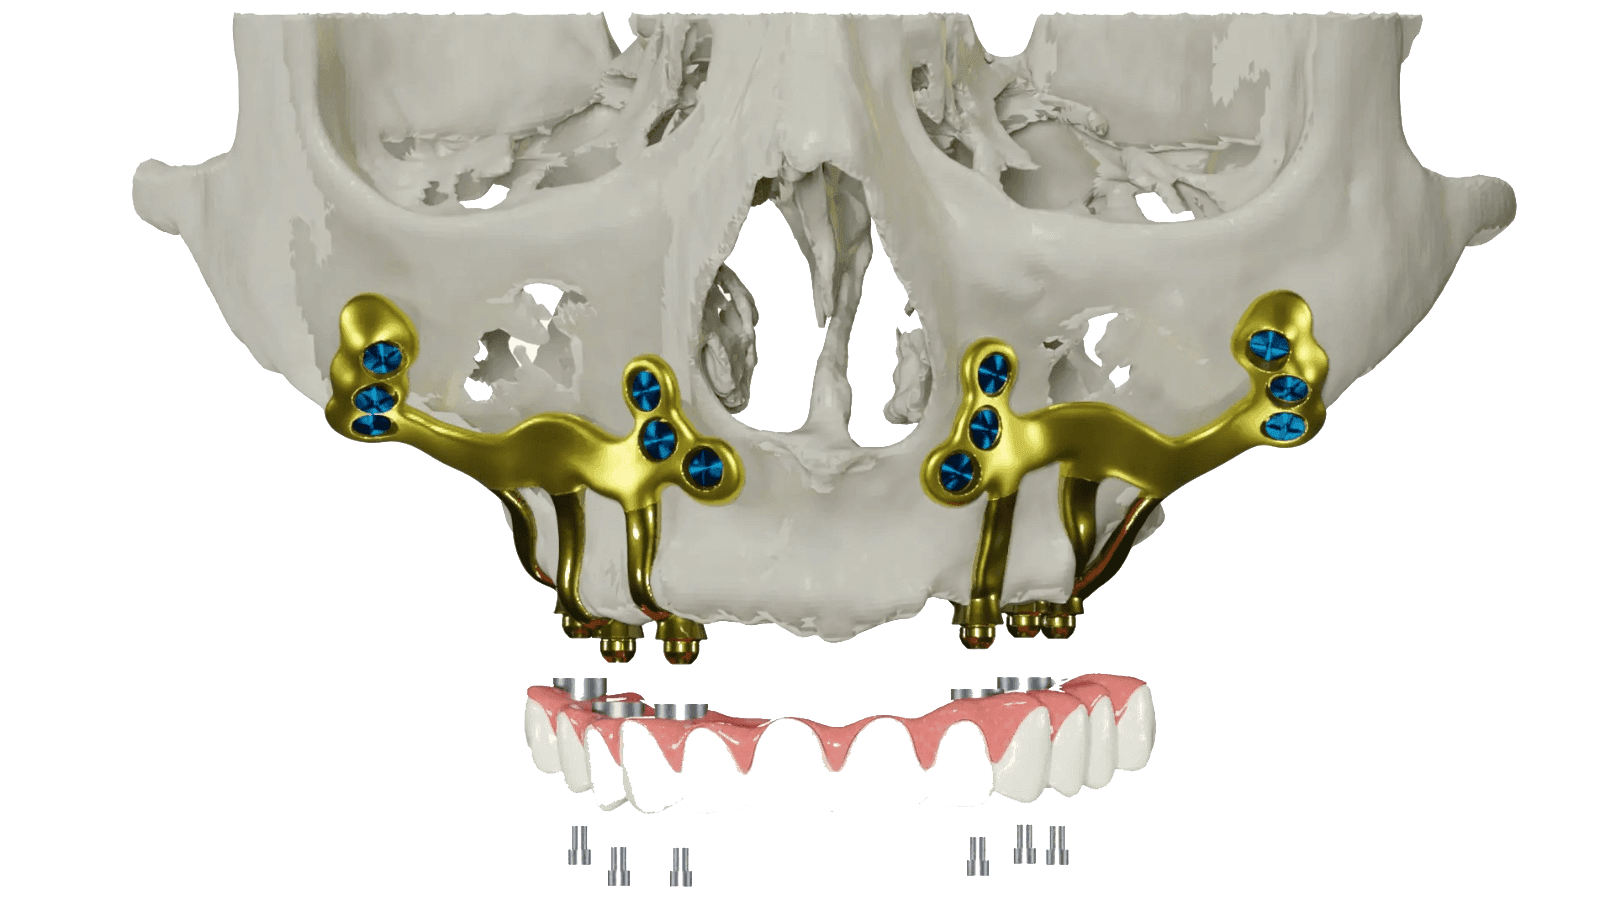

Severe bone loss in the jaw can occur in patients for various reasons (periodontal disease, trauma, oral hygiene issues, etc.). For patients with advanced bone loss, traditional implant treatment may not always be possible due to insufficient bone volume. In such cases, subperiosteal implants offer an innovative and effective solution.

Subperiosteal implants are placed on surface of the jawbone, beneath the gum tissue, and can be used in both the upper and lower jaw. Because they do not require bone grafting, these custom-designed implant frameworks provide a stable and reliable foundation for fixed prosthetic restorations, even in cases with minimal remaining bone.

Subperiosteal implants are one of the procedures applied in patients with partial or total tooth loss (edentulism), under conditions where bone volume cannot be augmented with bone graft procedures, or when bone graft procedures are not preferred by the patients. They are custom-made implants. Unlike conventional implants, it is not a system placed into the bone, but rather an implant system placed on the bone surface and beneath the soft tissue called the periosteum, which covers/surrounds the bone surface.

This method offers patients the possibility of a fixed prosthesis in a short time, thanks to the titanium frame structure placed specifically on the bone (under the periosteum). In this way, dental implant treatments can be performed for patients who have experienced severe bone loss due to reasons such as periodontal disease or trauma.